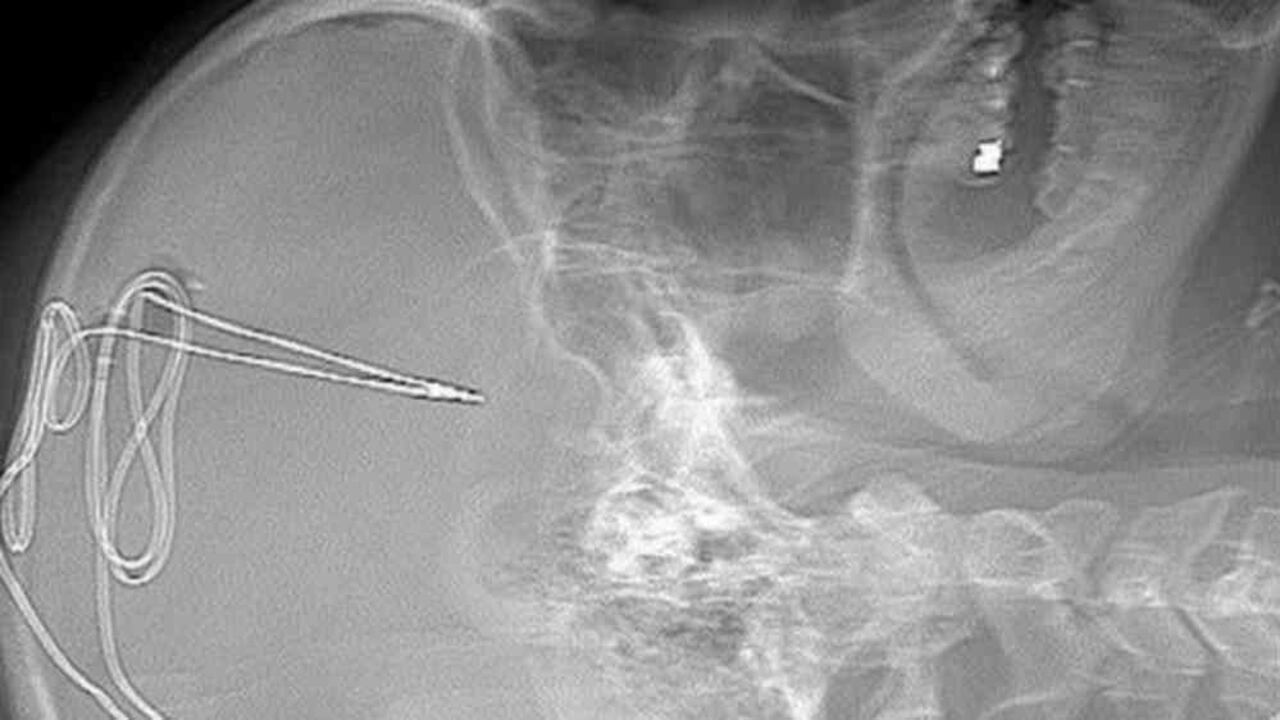

El doctor Ali Rezai y su equipo llevaron a cabo el procedimiento a principios de este mes. FOTO: HOSPITAL UNIVERSIDAD DE VIRGINIA/ BBC.

El proceso comienza con una serie de escáneres cerebrales. Después se practica la cirugía. Para ello se hace un pequeño agujero en el cráneo para insertar un electrodo de 1 milímetro en un área específica del cerebro que regula impulsos como la adicción y el autocontrol.

Se inserta una batería debajo de la clavícula, de manera que la actividad cerebral se monitorea de manera remota por el equipo de médicos, fisiólogos y expertos en adicción para ver si el anhelo de consumir la sustancia disminuye.